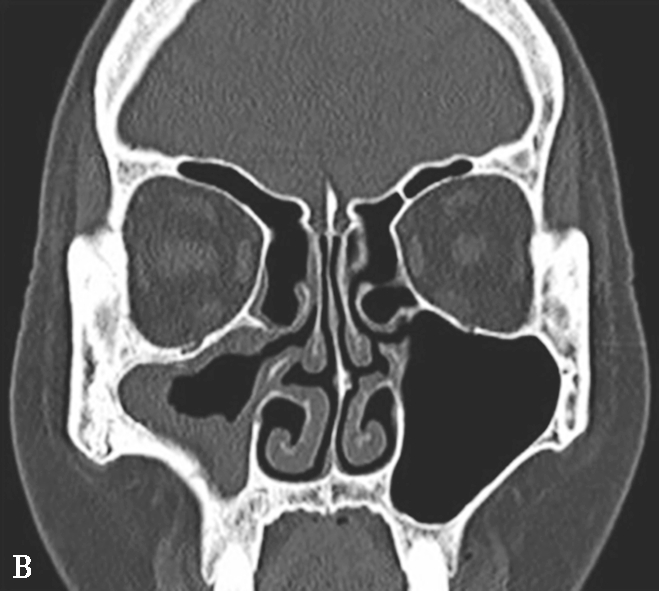

①平扫表现:鼻窦黏膜增厚,轻度2~5mm,中度5~10mm,重度> 10mm。黏膜下囊肿可见。严重者窦腔实变。窦壁骨质硬化、肥厚(图1-3-20A~C)。②增强扫描表现:边缘黏膜明显强化。

5.MRI表现

①T 1 WI表现:低信号多见,亦可为等或高信号。②T 2 WI表现:高信号多见,亦可为等或低信号,依分泌物内自由水与蛋白质含量而定。信号可不均匀。③增强扫描表现:边缘黏膜明显强化(图1-3-20D~F)。

图1-3-20 慢性鼻窦炎

A~C.横断面、冠状面及矢状面CT平扫,示右侧额窦、上颌窦黏膜增厚,窦腔内可见软组织密度影,窦口鼻道复合体狭窄,右侧上颌窦窦壁骨质增生硬化、肥厚;D~F.同一患者横断面MR T 2 WI、T 1 WI及横断面增强T 1 WI,示右侧上颌窦黏膜增厚,呈T 1 WI等信号、T 2 WI高信号影,增强扫描示右侧上颌窦黏膜线样强化